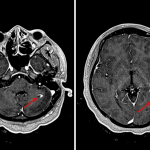

- Numerous supratentorial and infratentorial periventricular and juxtacortical T2/FLAIR hyperintense lesions including extensive lesions throughout the brainstem, many of which have associated T1 hypointensity

- Incomplete ring enhancement associated with lesions in the left cerebellar hemisphere, left parietal lobe, left frontal lobe, and right cingulate gyrus

- Multiple sclerosis with active demyelination

Extensive supratentorial and infratentorial white matter lesions with appearance and distribution consistent with the reported history of multiple sclerosis. Several lesions in the left cerebellar hemisphere, left frontal and parietal lobes, and right cingulate gyrus have associated enhancement concerning for active demyelination.